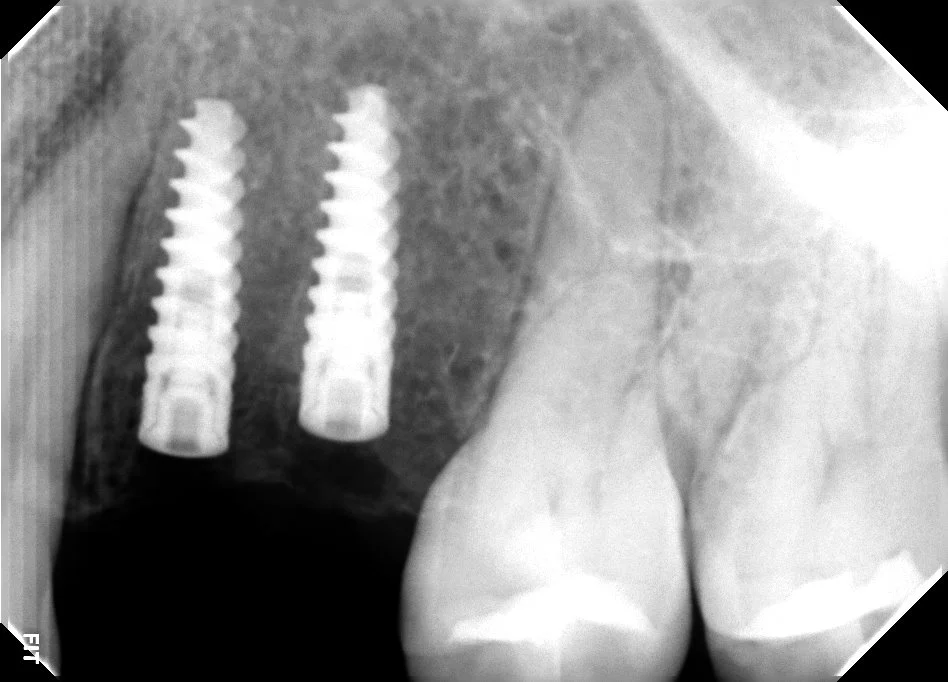

Implante dental explicado: pilar, pilar protésico y corona en Veracruz

Historia clínica, fotos, escaneo 3D y radiografía. Planeación guiada para posición ideal del implante.